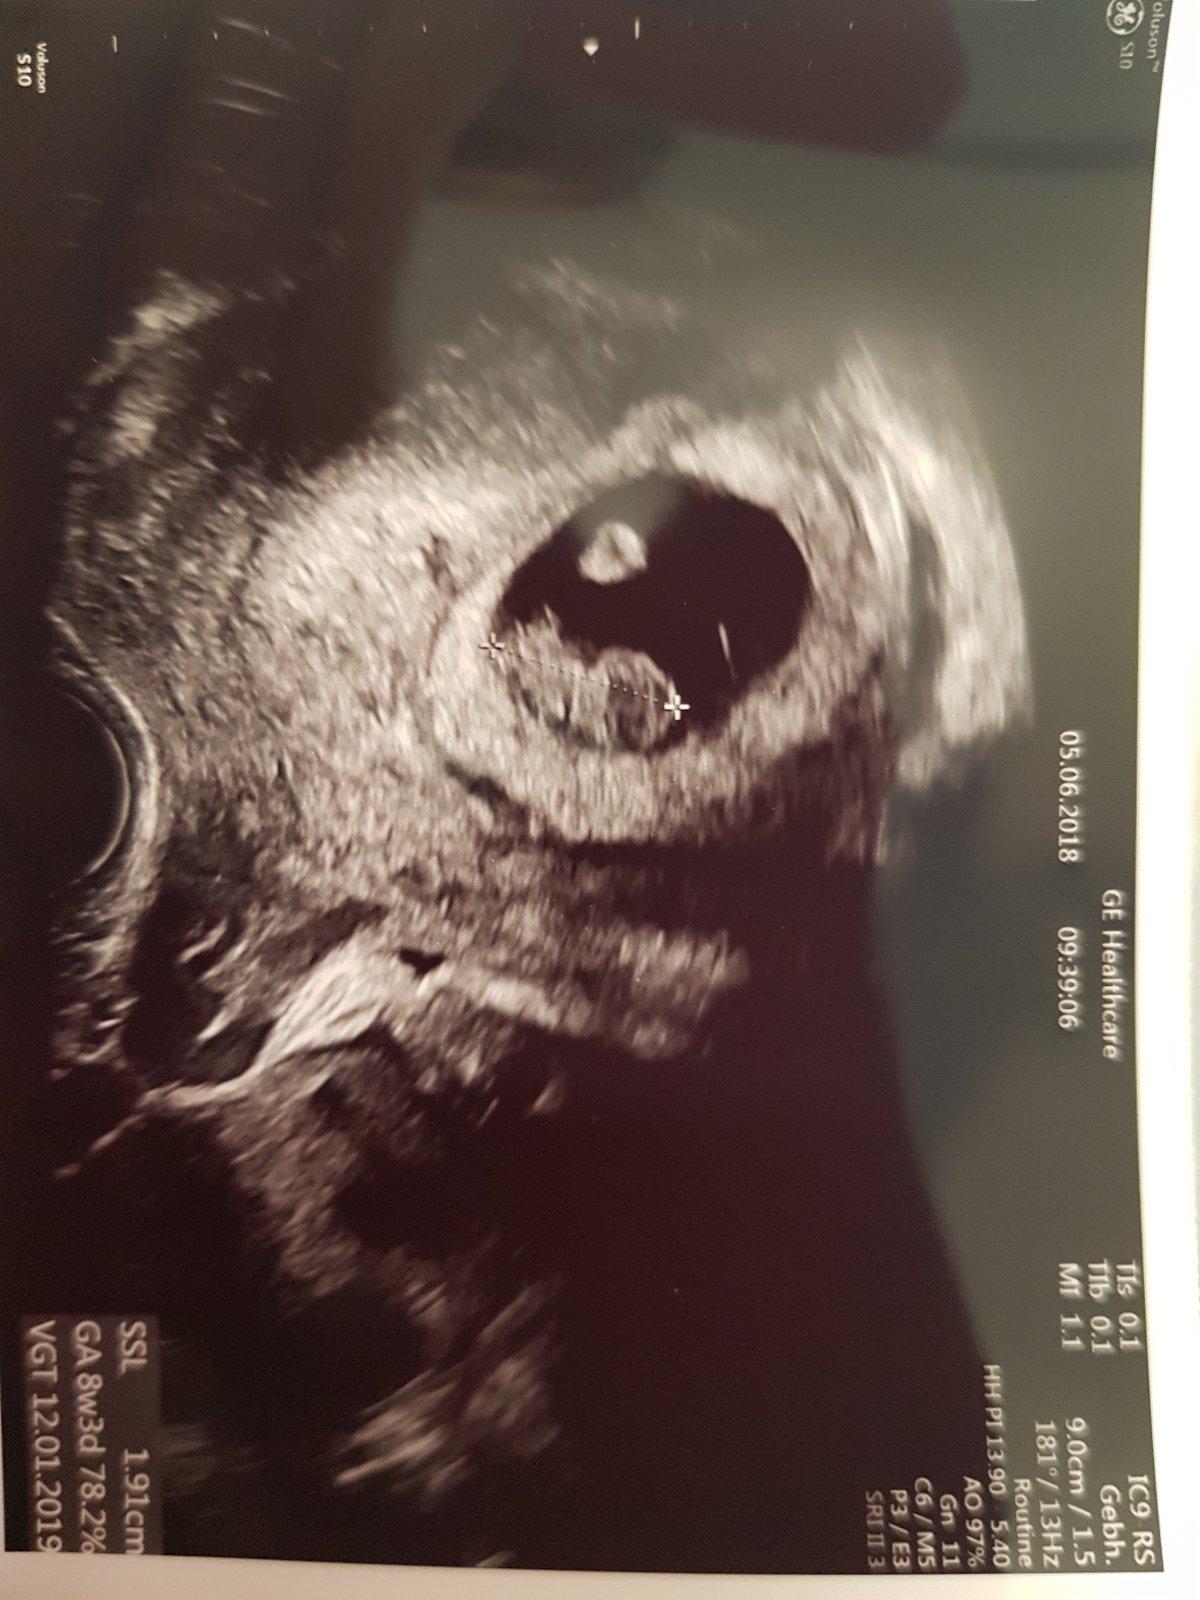

Ahoj holky, tak včera na ultrazvuku. Byla jsem z toho trochu špatná, měla jsem být 8+1 a podle ultrazvuku 7+3, přitom zezačátku to hezky odpovídalo, tak doufám, že to moje neustálý zvracení prcka nějak neohrozí☹. Má jen 11 mm. Ivanka měla v 7+5 14,3 mm.....ach jo, zase to moje porovnávání.... Ale srdíčko tluče jako o závod. Termín porodu zhruba 14.1.2019:-)